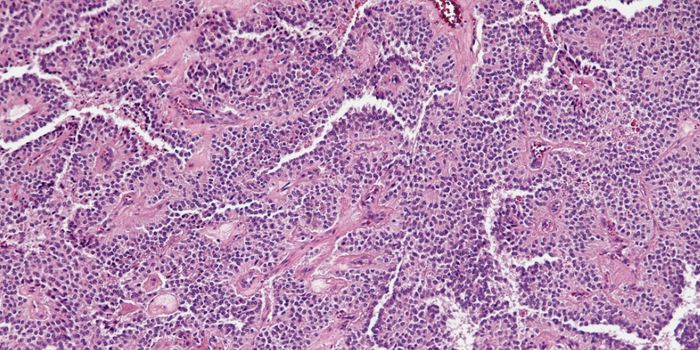

OCT 07, 2021CancerNeuroblastoma is a cancer of immature nerve cells found in various areas, including the adrenal glands, neck, chest ...

AUG 06, 2016CancerIn an effort to nip lymphomas before it becomes lethal to patients, scientists at the University of Geneva have develope ...

JUN 12, 2018CancerCD44 is a known cell surface protein involved in numerous interactions; it is overexpressed in cancerous tissue and its ...